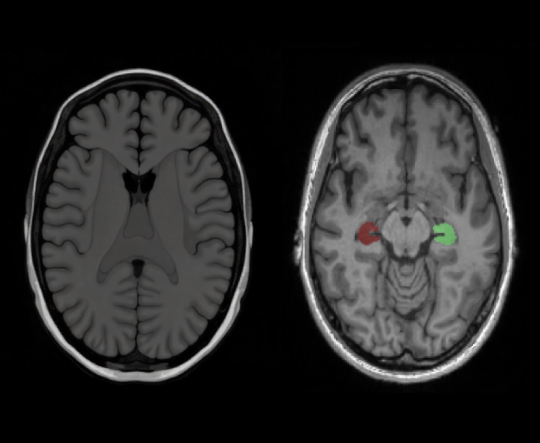

Alzevita is a cloud-based, AI-powered medical image processing software as a medical device intended to assist neurologists, radiologists and researchers with expertise in the analysis of 3D brain MRI scans. The software performs fully automated segmentation and volumetric quantification of the hippocampus, a brain structure involved in memory and commonly affected by neurodegenerative conditions.

Alzevita is designed to replace manual hippocampal segmentation workflows with a fast, reproducible, and standardized process. It provides quantitative measurements of hippocampal volume, enabling consistent outputs that can assist healthcare professionals in evaluating structural brain changes. The software supports image interpretation of MRI scans in both clinical and research setting.

AI-Based Segmentation

The software performs fully automated segmentation and volumetric quantification of the hippocampus, a brain structure involved in memory and commonly affected by neurodegenerative conditions.

Volumetric Analysis

It provides quantitative measurements of hippocampal volume, enabling consistent outputs that can assist healthcare professionals in evaluating structural brain changes.